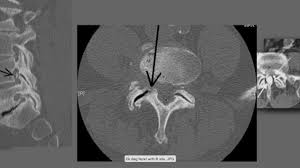

Ct And Mri Determination Of Intermuscular Space Within Lumbar Paraspinal Muscles At Different Intervertebral Disc Levels

Ct And Mri Determination Of Intermuscular Space Within Lumbar Paraspinal Muscles At Different Intervertebral Disc Levels from journals.plos.org